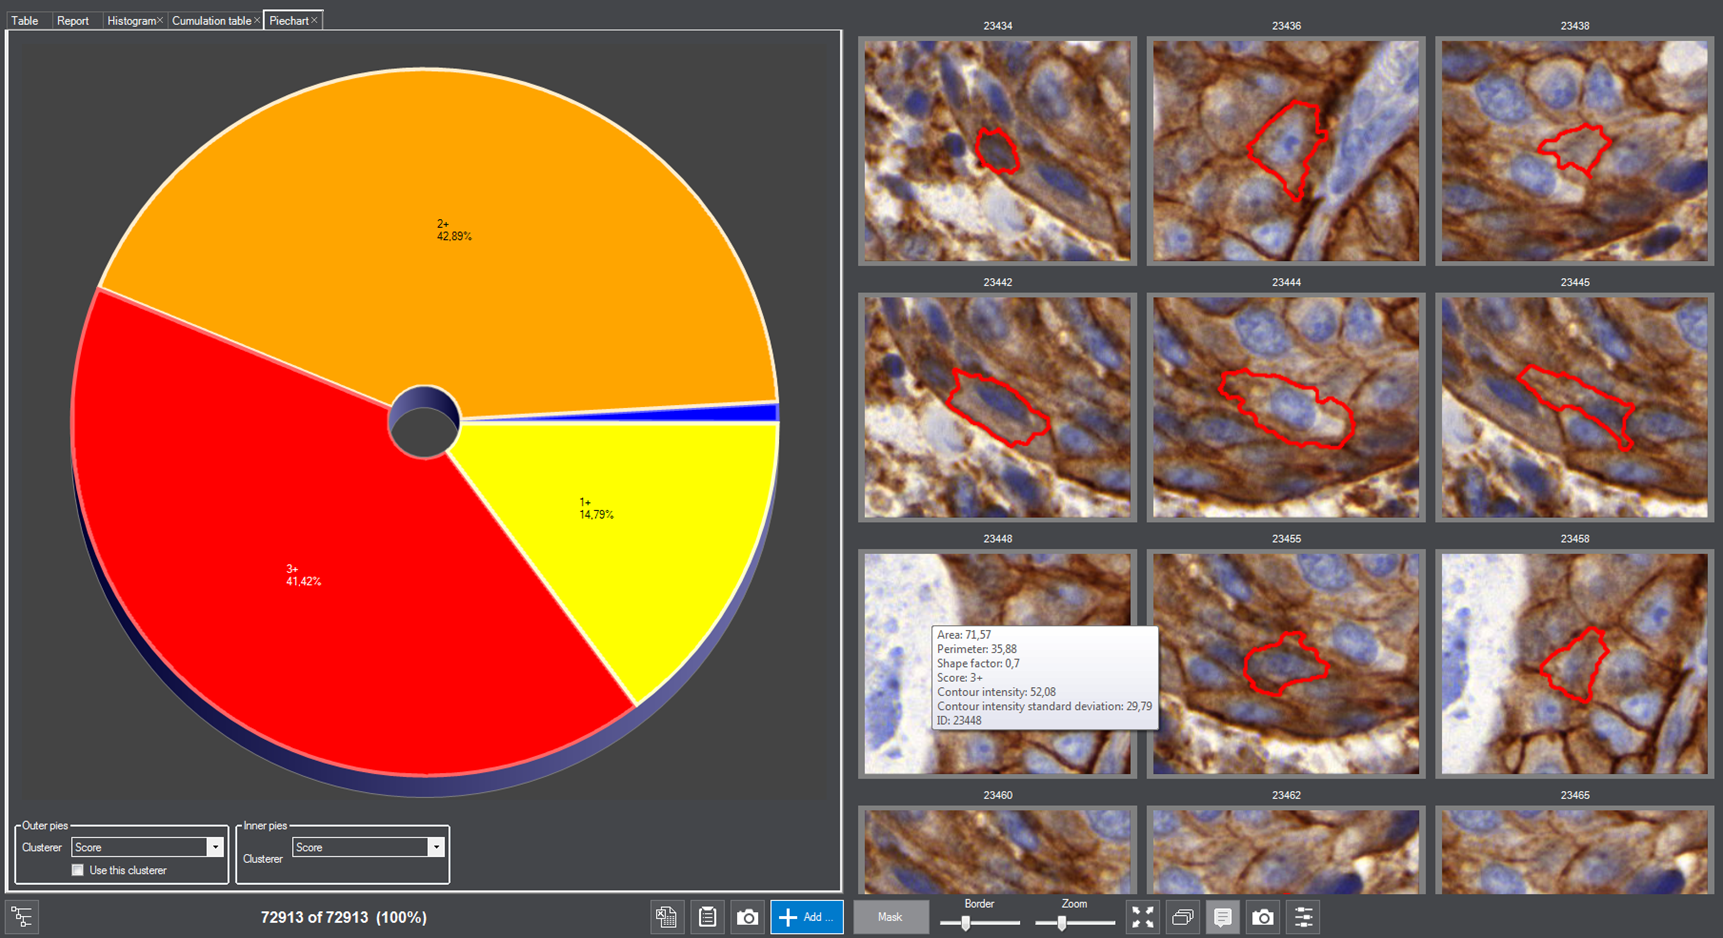

MembraneQuant is a cell membrane detection software application that can be used for the quantification of IHC stained histological samples. This module measures cell morphology and stain density, reports intensity-based core ranges, overall scores and positivity percentages (including H-Score), distinguishing the continuous membrane stain from the moderate stain.

This module has IVD approval for the quantification of Her2 expression in breast tissue samples.